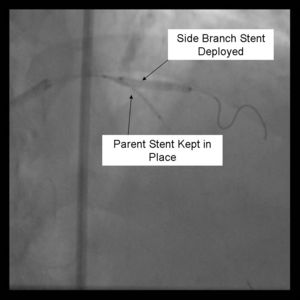

7) The side branch stent is deployed.

8) Angiography should now be performed to ensure adequate side branch coverage and stent deployment. Distal edge dissections or disease should be addressed before parent stent deployment. Once complete, the side branch wire is removed.

9) The parent stent is deployed.